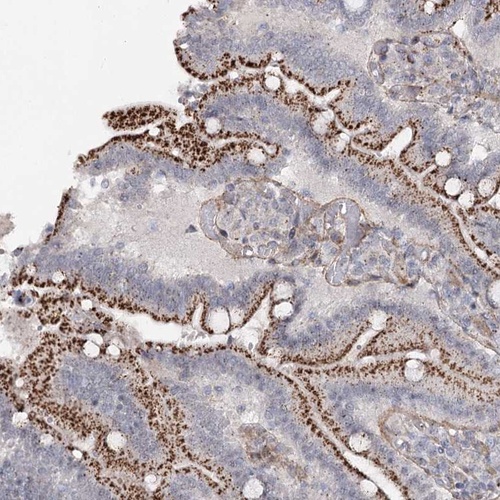

Immunohistochemical staining of human duodenum shows distinct cytoplasmic positivity with a granular pattern in glandular cells.